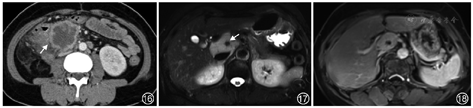

2.平滑肌肉瘤:起源于腹膜后平滑肌组织或腹膜后大静脉管壁,为腹膜后第二常见肉瘤(约占28%),其发病年龄较神经源性肿瘤患者更大,且预后更差。平滑肌肉瘤最常见生长方式为完全血管外生长的肿瘤,少数肿瘤呈血管外和血管内同时受累,完全血管内生长(常发生于下腔静脉)罕见[12]。组织病理学可见典型交错排列、边缘锐利的梭形细胞束。临床常无症状,常为影像学偶然发现。肿瘤较大时可引起临床压迫性症状。影像上通常表现为较大的边界不清的软组织肿块,内部可见坏死、出血或囊变区(图16)。钙化少见,可见于罕见的骨肉瘤分化病例。

3.Castleman病:即巨淋巴结增生症,病因不明,以淋巴细胞增殖为特征,约12%病例累及腹膜后。临床上可分为局灶型和弥漫型,病理上分为透明血管型、浆细胞型、人类疱疹病毒相关和多中心型[13]。局灶型Castleman病主要为透明血管型,手术切除预后良好。弥漫型多见于浆细胞型,预后差,需要系统性治疗。局灶型好发于30~50岁患者,表现为较大的孤立性软组织肿块,可伴周围卫星灶,边界清晰,内部可见斑点状钙化(图17)、囊变或坏死区。肿块T1WI呈等信号、T2WI呈高信号,增强后动脉期明显强化,通常均匀强化,并持续至延迟期(图18)。可伴肝脾肿大、腹腔积液、腹膜后筋膜增厚。